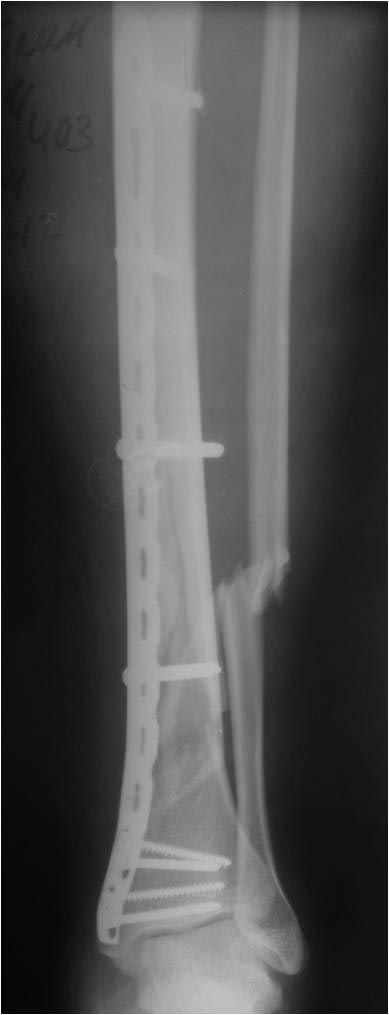

[Ortho] Деформация фиксатора после падения

первичные снимки и остальные качеством получше.

Имя     : 123.jpg

Тип     : image/jpg

Размер  : 27956 байтов

Url     : http://weborto.net:8080/pipermail/ortho/attachments/20121105/5ddbb42f/attachment-0005.jpg